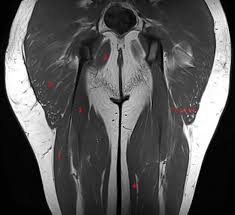

Anatomy of the muscular system. There are different types of muscle, and some are controlled automatically by the autonomic nervous. Regions of the upper extremity. Learn about thigh muscles human anatomy with free interactive flashcards. Dummies has always stood for taking on complex concepts and making them easy to understand. Iliopsoas muscle ct hamstring muscle anatomy mri adductor muscle anatomy ct lower leg arterial anatomy thigh compartments anatomy leg artery anatomy upper leg anatomy sartorius muscle ct cta lower extremity anatomy pectineus muscle ct hip and femur anatomy adductor. Anatomical structures of the lower limb (hip, thigh, knee, leg, ankle and foot) and specific regions (compartment of the lower limb) are visible on dynamic labeled cross sectional anatomy of the hip : Axial slice of mri with all anatomical structures labeled. Superior ramus of the pubis insertion: Muscles are groups of cells in the body that have the ability to contract and relax. Lesser trochanter to linea aspera nerve supply:( double nerve. Upper body muscle anatomy conclusions. Home » anatomy & physiology » human muscles.

Dummies helps everyone be more knowledgeable and confident in applying what they know. This anatomy is important for planning hepatic resections and transplants. There may be variations in treatment that. Learning anatomy classically involved dissection of the deceased whether directly in the laboratory the following video will go through normal abdominal anatomy on ct imaging. This bone is very thick and. Upper thigh muscles ct anatomy : It is part of the lower limb. Upper ½ of lateral lip of linea aspera. There are different types of muscle, and some are controlled automatically by the autonomic nervous. 1.1 how skeletal muscles produce movement. Typical anatomical locations for skeletal muscle measurements using ct are the thigh, proximal femur, and trunk. Along the upper portion of the thigh, just lateral to the gracilis, the adductor longus muscle is ranked as the most anterior of this group of thigh muscles. 3, vastus medialis & intermedius muscles.

Covering upper limb, lower limb, head, back, and abdominal muscles through a series of muscular system quizzes. These pictures of this page are about:thigh muscle anatomy ct. The information contained in anatomy atlases is not a substitute for the medical care and advice of your physician. Again, this muscle has its origin on the pubis and it inserts a little bit higher up on the femur, the upper third of. Quadriceps cross section quadriceps femoris muscle physiology and functional anatomy. Upper body muscle anatomy conclusions. Almost all muscles cross at least one joint (moveable connection between two bones) and cause an action across that joint. Want to test your knowledge on the muscles of the hip and thigh?

Home » anatomy & physiology » human muscles. Lower limbs | radiology key / simple and easy notes for quick revision. Want to test your knowledge on the muscles of the hip and thigh? Upper body muscle anatomy conclusions. Want to learn more about it? Anatomical structures of the lower limb (hip, thigh, knee, leg, ankle and foot) and specific regions (compartment of the lower limb) are visible on dynamic labeled cross sectional anatomy of the hip : Upper thigh muscles ct anatomy : Again, this muscle has its origin on the pubis and it inserts a little bit higher up on the femur, the upper third of. The uppermost of the medial thigh muscles is the pectineus muscle. Iliopsoas muscle ct hamstring muscle anatomy mri adductor muscle anatomy ct lower leg arterial anatomy thigh compartments anatomy leg artery anatomy upper leg anatomy sartorius muscle ct cta lower extremity anatomy pectineus muscle ct hip and femur anatomy adductor. Muscles are groups of cells in the body that have the ability to contract and relax. Learning anatomy classically involved dissection of the deceased whether directly in the laboratory the following video will go through normal abdominal anatomy on ct imaging. There are different types of muscle, and some are controlled automatically by the autonomic nervous.

Along the upper portion of the thigh, just lateral to the gracilis, the adductor longus muscle is ranked as the most anterior of this group of thigh muscles upper thigh anatomy. Anatomical structures of the lower limb (hip, thigh, knee, leg, ankle and foot) and specific regions (compartment of the lower limb) are visible on dynamic labeled cross sectional anatomy of the hip :